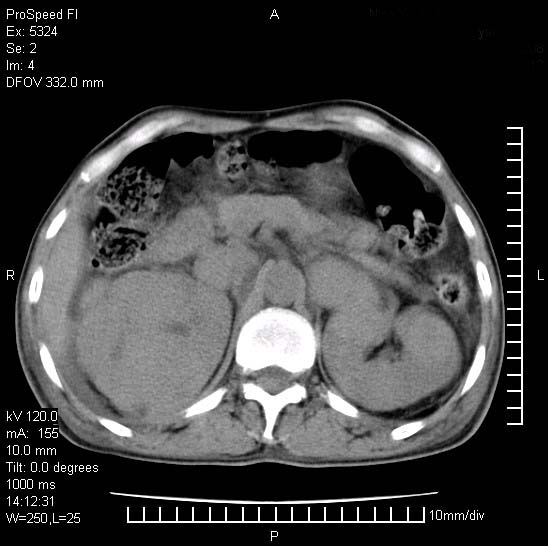

患者阴囊肿大14月,腰痛2个月,咳嗽,咳痰1周,患者现在肾功异常,做增强有些担心,我们用的是欧乃派克.

右侧肾癌伴腹膜后淋巴结转移!

右侧肾癌后腹膜转移,腹腔少量积液

腹膜后淋巴结肿大包饶腔静脉,双肾病变,建议增强

双肾均有软组织密度舯物,腹膜后淋巴结肿大包饶腔静脉------考虑为恶性占位病变,转移瘤可能。

支持:双肾均见软组织密度肿块影,腹膜后淋巴结肿大包绕腔静脉------考虑为恶性占位病变,转移瘤可能。

1)考虑双肾恶性肿瘤(肾癌?)。2)腹膜后淋巴结肿大,多为肿瘤转移所致。

腹腔积液,双肾均有稍高密度肿块,主动脉旁广泛淋巴结肿大,融合,无显著肿块坏死征像,多考虑淋巴瘤累及双肾,不排除肾癌伴转移(肾癌这么大应该较多坏死了),另阴囊肿大,不知是实质肿大还是阴囊积液,如是是积液,多为腹腔肿块压近睾丸静脉所致,如是是实性的,多为淋巴瘤

1、淋巴瘤,双肾转移瘤;2、双侧肾癌,伴有腹膜后淋巴结转移。

双肾均有软组织肿块伴腹膜后淋巴结肿大融合,右侧结肠旁沟积液;考虑恶性肿瘤。转移瘤?淋巴瘤?

双肾增大,腹膜后多发肿大淋巴结影.首先考虑淋巴瘤.

双肾增大,结合腹膜后淋巴结肿大,考虑双肾恶性肿瘤并转移可能。

双肾癌并腹膜后淋巴结转移

考虑恶性淋巴瘤侵及双肾,腹膜后淋巴结肿大。